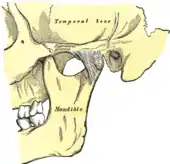

![]() | |

| Temporomandibular joint | |

Temporomandibular joints

The temporomandibular joints are the dual articulation of the mandible with the skull. Each TMJ is classed as a "ginglymoarthrodial" joint since it is both a ginglymus (hinging joint) and an arthrodial (sliding) joint,[41] and involves the condylar process of the mandible below, and the articular fossa (or glenoid fossa) of the temporal bone above. Between these articular surfaces is the articular disc (or meniscus), which is a biconcave, transversely oval disc composed of dense fibrous connective tissue. Each TMJ is covered by a fibrous capsule. There are tight fibers connecting the mandible to the disc, and loose fibers which connect the disc to the temporal bone, meaning there are in effect 2 joint capsules, creating an upper joint space and a lower joint space, with the articular disc in between. The synovial membrane of the TMJ lines the inside of the fibrous capsule apart from the articular surfaces and the disc. This membrane secretes synovial fluid, which is both a lubricant to fill the joint spaces, and a means to convey nutrients to the tissues inside the joint. Behind the disc is loose vascular tissue termed the "bilaminar region" which serves as a posterior attachment for the disc and also fills with blood to fill the space created when the head of the condyle translates down the articular eminence.[42] Due to its concave shape, sometimes the articular disc is described as having an anterior band, intermediate zone and a posterior band.[43] When the mouth is opened, the initial movement of the mandibular condyle is rotational, and this involves mainly the lower joint space, and when the mouth is opened further, the movement of the condyle is translational, involving mainly the upper joint space.[44] This translation movement is achieved by the condylar head sliding down the articular eminence, which constitutes the front border of the articular fossa.[35] The function of the articular eminence is to limit the forwards movement of the condyle.[35] The ligament directly associated with the TMJ is the temporomandibular ligament, also termed the lateral ligament, which really is a thickening of the lateral aspect of the fibrous capsule.[35] The stylomandibular ligament and the sphenomandibular ligament are not directly associated with the joint capsule. Together, these ligaments act to restrict the extreme movements of the joint.[45]